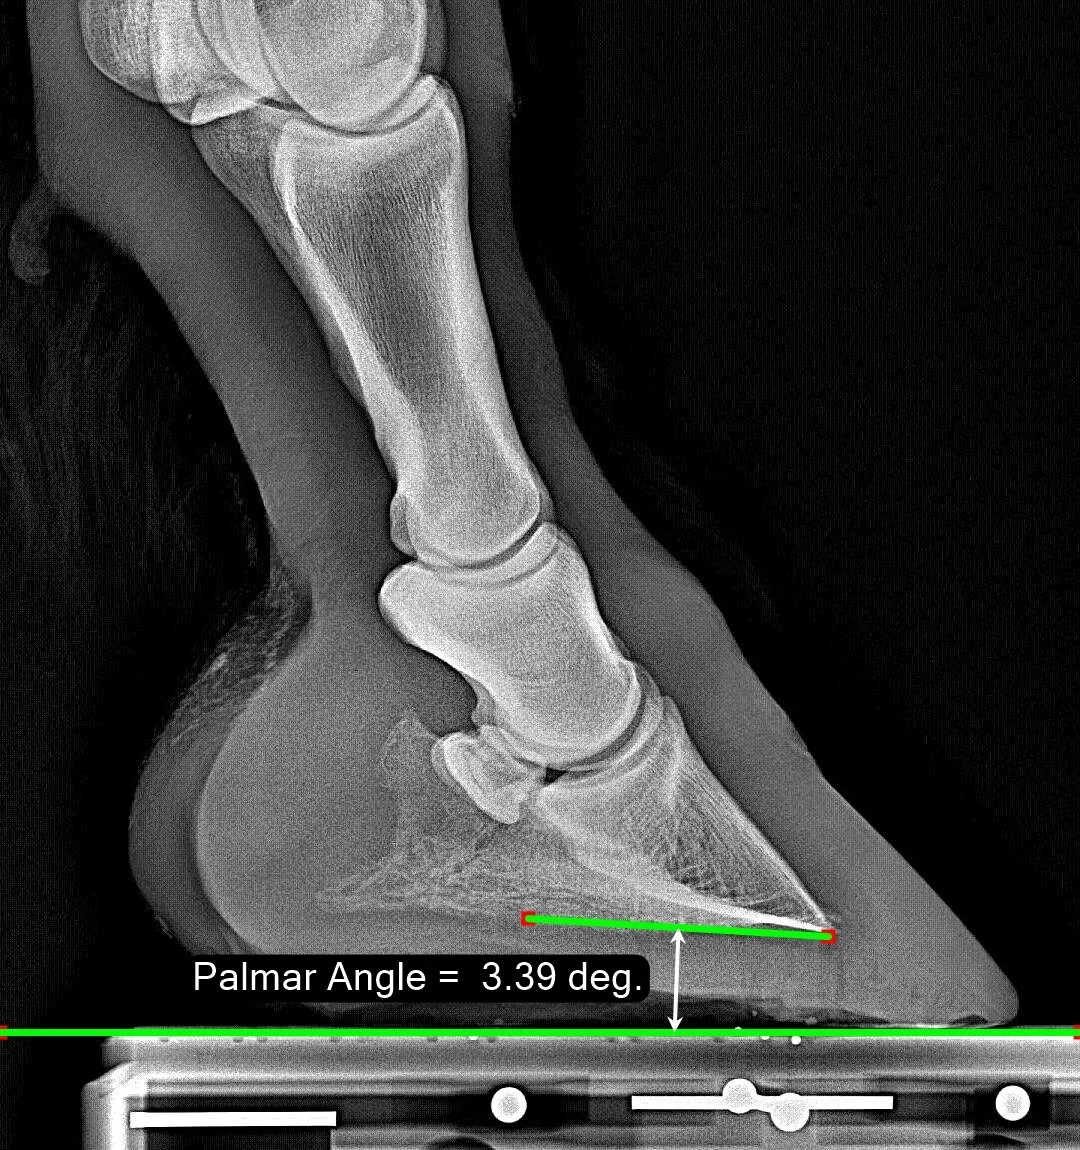

Palmar Angle

The Palmar Angle describes the shallow angle between the bottom of P3 and the ground. It grows more positive as the heels are raised. If the heels are very low, the Palmar Angle can become negative.

Our ‘normal range’ is from 1.3 degrees up to 9.7 degrees, with the median at 4.7 degrees. The black vertical line shows the value for this image. Our reports also show the Palmar Angle on page 1 with the distribution colored by quartiles. More on Palmar Angle.